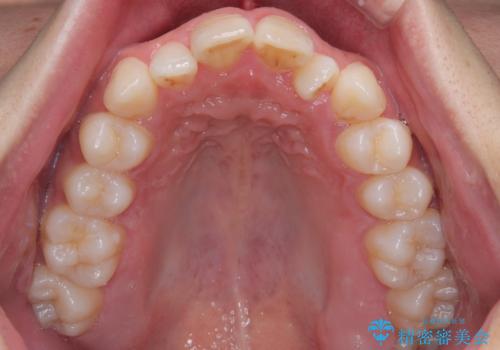

- 「上下の前歯がガタガタしているのが気になる」とのことで来院された患者様です。

上下顎前歯部に叢生(歯の重なり・ガタつき)を認め、見た目だけでなく、歯磨きのしにくさも気にされて来院されました。